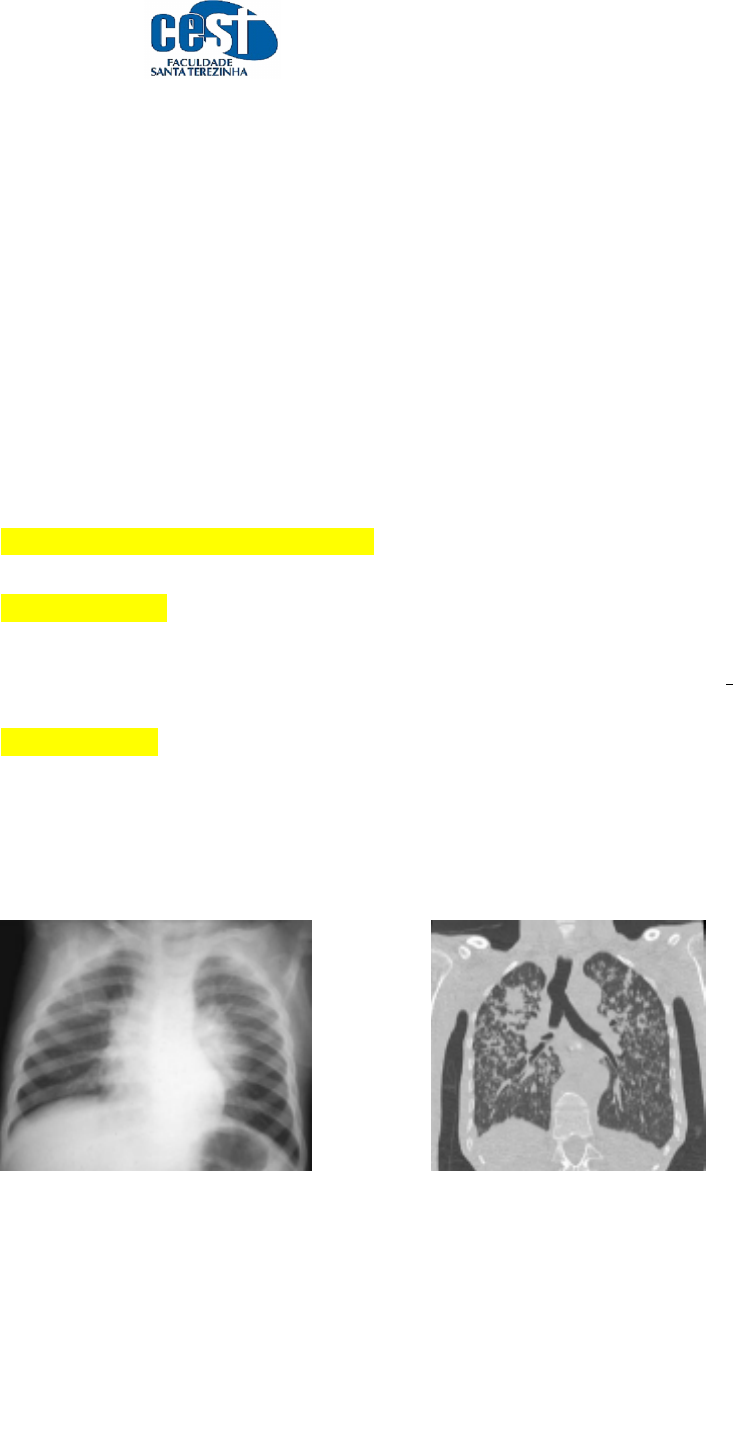

3. Responda qual o método diagnóstico correspondente às imagens abaixo:

A. RADIOGRAFIA B. TOMOGRAFIA COMPUTADORIZADA